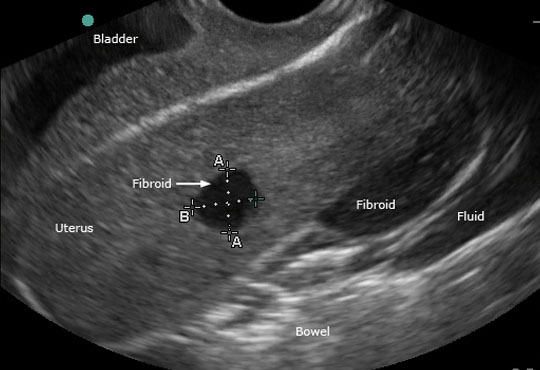

It is performed through 3 to 6 Mhz transducer (probe) We can fairly assess many abdominal and pelvic organs. (i. e. Liver, Gall bladder, Kidneys, Reproductive Organ) to diagnose (confirm or to rule out) various medical diseases / ailments through painless comfortable accurate ultrasound scanning.